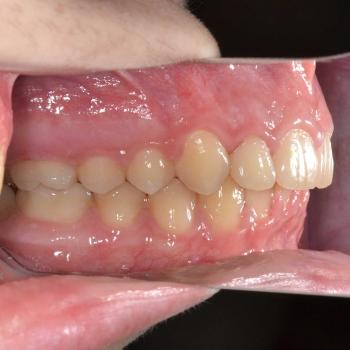

Balázs és édesanyja konzultáció céljából keresett fel, hogy egyértelműen kiderüljön számukra szükséges-e a fogszabályozó kezelés vagy sem. Már rögtön az első vizsgálat alkalmával fény derült több olyan problémára is, melyek fogszabályozást igényelnek. Ilyen volt például a súlyos mélyharapás, a hátrafelé dőlő felső metszők, illetve az Angle II. osztályú harapási eltérés is. A mintavétel, a röntgenek és a fotók kiértékelése után további problémaként merült fel a felső fogív szűkülete és a kismetszők méretaránytalansága, azaz a túlzott keskenységük.

A kezelést Quadhelix fogszabályozóval kezdtük el a felső fogív tágítása érdekében. Ezután került felragasztásra az alsó és felső fogívre a Balázs és szülei által kiválasztott fém önligírozó fogszabályozó. Ezen túlmenően Bite turbo harapásemelő segített a mélyharapás, intermaxillaris gumihúzás pedig az Angle II. osztályú harapási eltérés korrigálásában. A fogak méretaránytalansága miatt a kezelés végén a kismetszőket tömőanyaggal építettük fel, hogy a tökéletes harapáshoz résmentes fogazat társuljon. A fogak felépítéséhez az adott fogakat nem kell megfúrni, a tömőanyag kizárólag ragasztásos módszerrel rögzül, így nem károsodik a fogzománc.